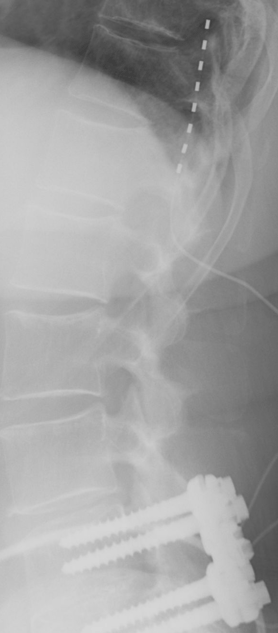

Phase de test avec une électrode chirurgicale pour soulager des douleurs chroniques post-chirurgicales

Electrode per-cutanée visant à soulager des douleurs chroniques post-chirurgicales